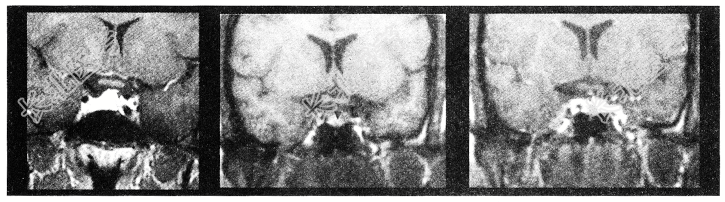

- 单项选择题女性患者,38岁。头痛、闭经, MRI检查如图,选择最可能的诊断为

A、垂体微腺瘤

B、转移瘤

C、垂体脓肿

D、垂体囊肿

E、垂体梗死